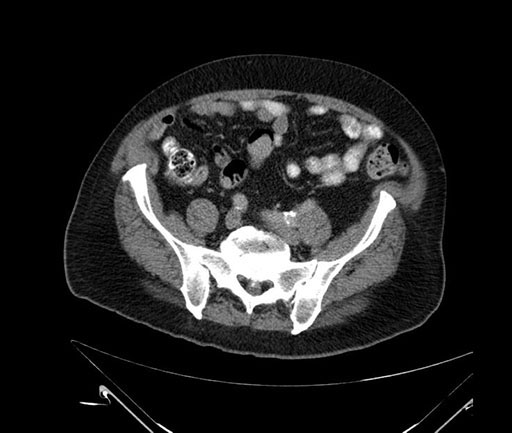

Imaging Analysis

Look through the patient's CT scan to identify any areas of concern for the necessary procedure.

Based on your CT findings, which issue(s) would give reason for "planned slowing down moment(s)" in this case?

Considering a standard Whipple procedure, what step(s) of the operation would you do differently in this case?